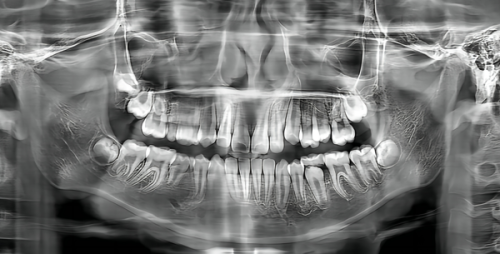

设备方面,医院配备数字化口腔全景机和口腔CBCT等精良仪器,能清晰捕捉口腔内部的每一个细微角落,为医生诊断提供无比精细的影像资料。即使是微小的龋齿或隐藏的牙根问题,也能被及时发现和处理。口腔CBCT进行三维立体成像,使得矫正方案的制定更加科学合理,确保每一副牙套都能精细推动牙齿移向预定位置,更终实现美观与功能兼备的矫正成效。